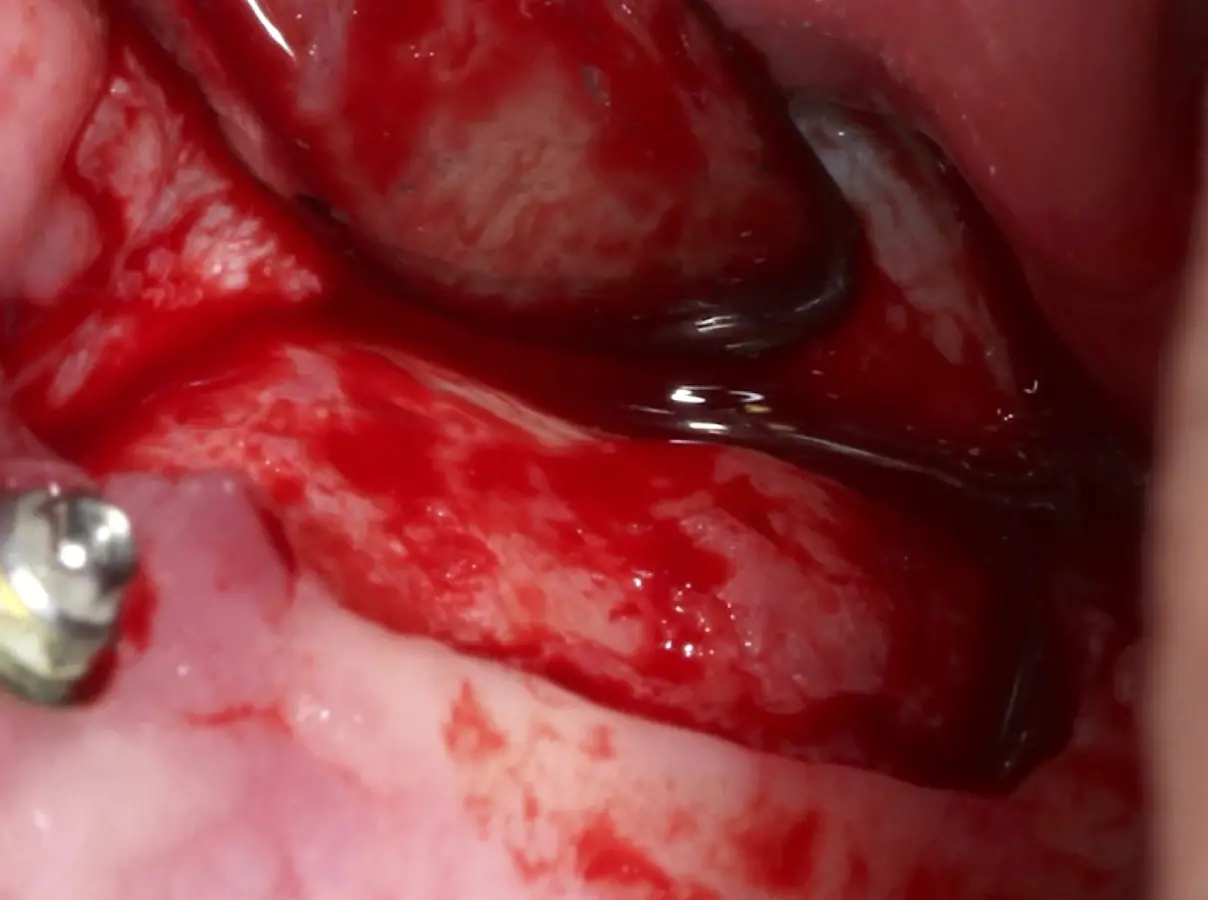

Se inicia la elevación de la membrana de Schneider con el inserto redondeado no cortante en forma de disco, empleando movimientos suaves. El levantamiento puede complementarse con elevadores convencionales, siguiendo la dirección mesiodistal. La fase de desprendimiento inicia con el piso y sigue hacia la pared mesial para terminar, y de ser necesario, hacia la pared posterior. Existen diversos insertos con angulaciones y longitudes para mayor accesibilidad16 (Figura 1).

Una vez elevado el piso sinusal según la planificación se realiza la evaluación clínica de la integridad de la membrana y de posibles desgarros a través de la maniobra de Valsalva.24 Consiste en pedir al paciente que respire profundamente y retenga el aire, cerrar la boca, apretar la nariz con los dedos y forzar la salida de aire. Al final de la prueba, es necesario mantener la presión entre 10 a 15 segundos. Se identificará la movilidad de la membrana y la ausencia de burbujas de aire para corroborar que no hay perforaciones. Dependiendo de la decisión clínica se puede optar por adicionar en la superficie de la membrana de Schneider membranas de colágeno o de plasma rico en fibrina (PRF) para dar mayor soporte durante la inserción del biomaterial de relleno óseo (Figura 10).